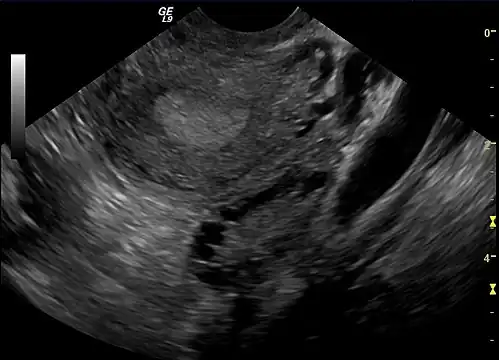

A polycystic ovary

• Polycystic ovaries: There are small cysts on one or both ovaries. Ovaries might enlarge and compress follicles surrounding the eggs. As a result, ovaries might fail to function regularly. This disease is related to the number of follicles per ovary each month, growing from the average range of 6–8 to double, triple, or more.

The syndrome acquired its most widely used name due to the common sign on ultrasound examination of multiple (poly) ovarian cysts. These "cysts" are immature ovarian follicles. The follicles have developed from primordial follicles, but this development has stopped ("arrested") at an early stage, due to the disturbed ovarian function. The follicles may be oriented along the ovarian periphery, appearing as a 'string of pearls' on ultrasound examination.[63]

Gynecologic ultrasonography first looks for small ovarian follicles.[75] To count as polycystic ovaries, at least 20 follicles need to be present, smaller than 9 mm. This used to be 12 in older diagnostic criteria.[16] A less clear marker of PCOS is enlarged ovaries.[75] Ovary need to be at least 10 cm3 to count.[16] For sexually active individuals or those that agree, a transvaginal ultrasound approach is preferred. Alternatively, AMH levels can be tested in the blood.[75] Laparoscopic examination may reveal a thickened, smooth, pearl-white outer surface of the ovary. This would usually be an incidental finding if laparoscopy were performed for some other reason, as it would not be routine to examine the ovaries in this way to confirm a diagnosis of PCOS.[78]

Ultrasonographic findings of polycystic ovaries are found in 8–25% of women who are not affected by the syndrome.[114][115][116][117] 14% women on oral contraceptives are found to have polycystic ovaries.[115] Ovarian cysts are also a common side effect of levonorgestrel-releasing intrauterine devices (IUDs).[118]